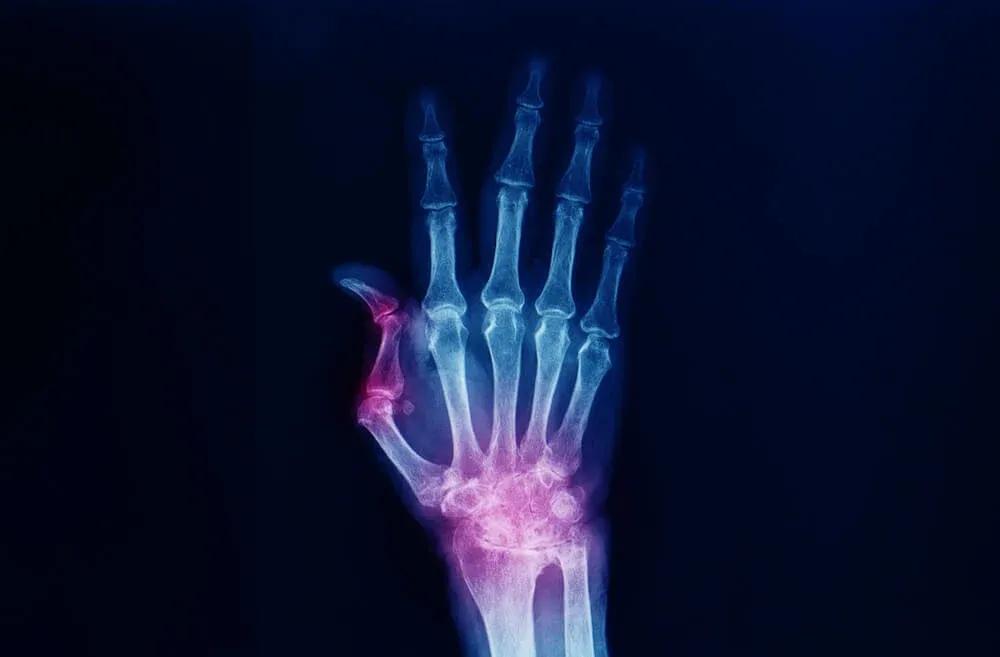

Osteoarthritis at the base of the thumb causes wear and tear on the cartilage between the bones. This causes pain when squeezing, gripping or turning. A brace provides stabilisation and restricts excessive movement. This allows the joint to rest more, which helps to reduce symptoms. As a result, you can continue to perform your daily activities with support.